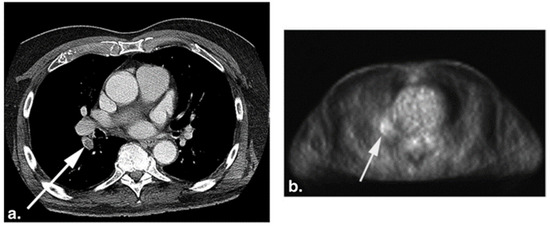

Figure 4.

CT (a) and the corresponding FDG-PET (b) images of a 75-year-old woman with a history of melanoma. The white arrows point to pulmonary embolism (PE) present in the right lower lobe segmental artery. Increased FDG uptake (b) is seen at the location of PE on the PET image (from Flavell et al. [119] with permission).

A retrospective study of thirteen patients with coincidental acute PE who underwent FDG-PET as a part of oncological treatment revealed that regions of acute pulmonary embolism have greater FDG activity compared to vessels without thrombi, with the shapes of the uptakes being focal or curvilinear. Specifically, the mean SUV of acute PE was 1.65 ± 0.61, while vessels with no thrombus was 1.15 ± 0.38, with a p-value of 0.009. An increased FDG uptake represented as a focal or curvilinear abnormality in the PET scans corresponded to the contrast-enhanced CT abnormality identified as PE [117]. Another retrospective study performed by Flavell et al. examining 59 FDG-PET/CT studies of patients with incidental PE similarly demonstrated that there was an increased focal FDG uptake within the pulmonary artery involved in or next to the PE compared to normal arteries. Furthermore, three of the cases with identified pulmonary infarct exhibited associated FDG avidity. Interestingly, one of the studies revealed that increased FDG uptake in the right ventricular wall was associated with saddle PE and bowing of the interventricular septum [119].